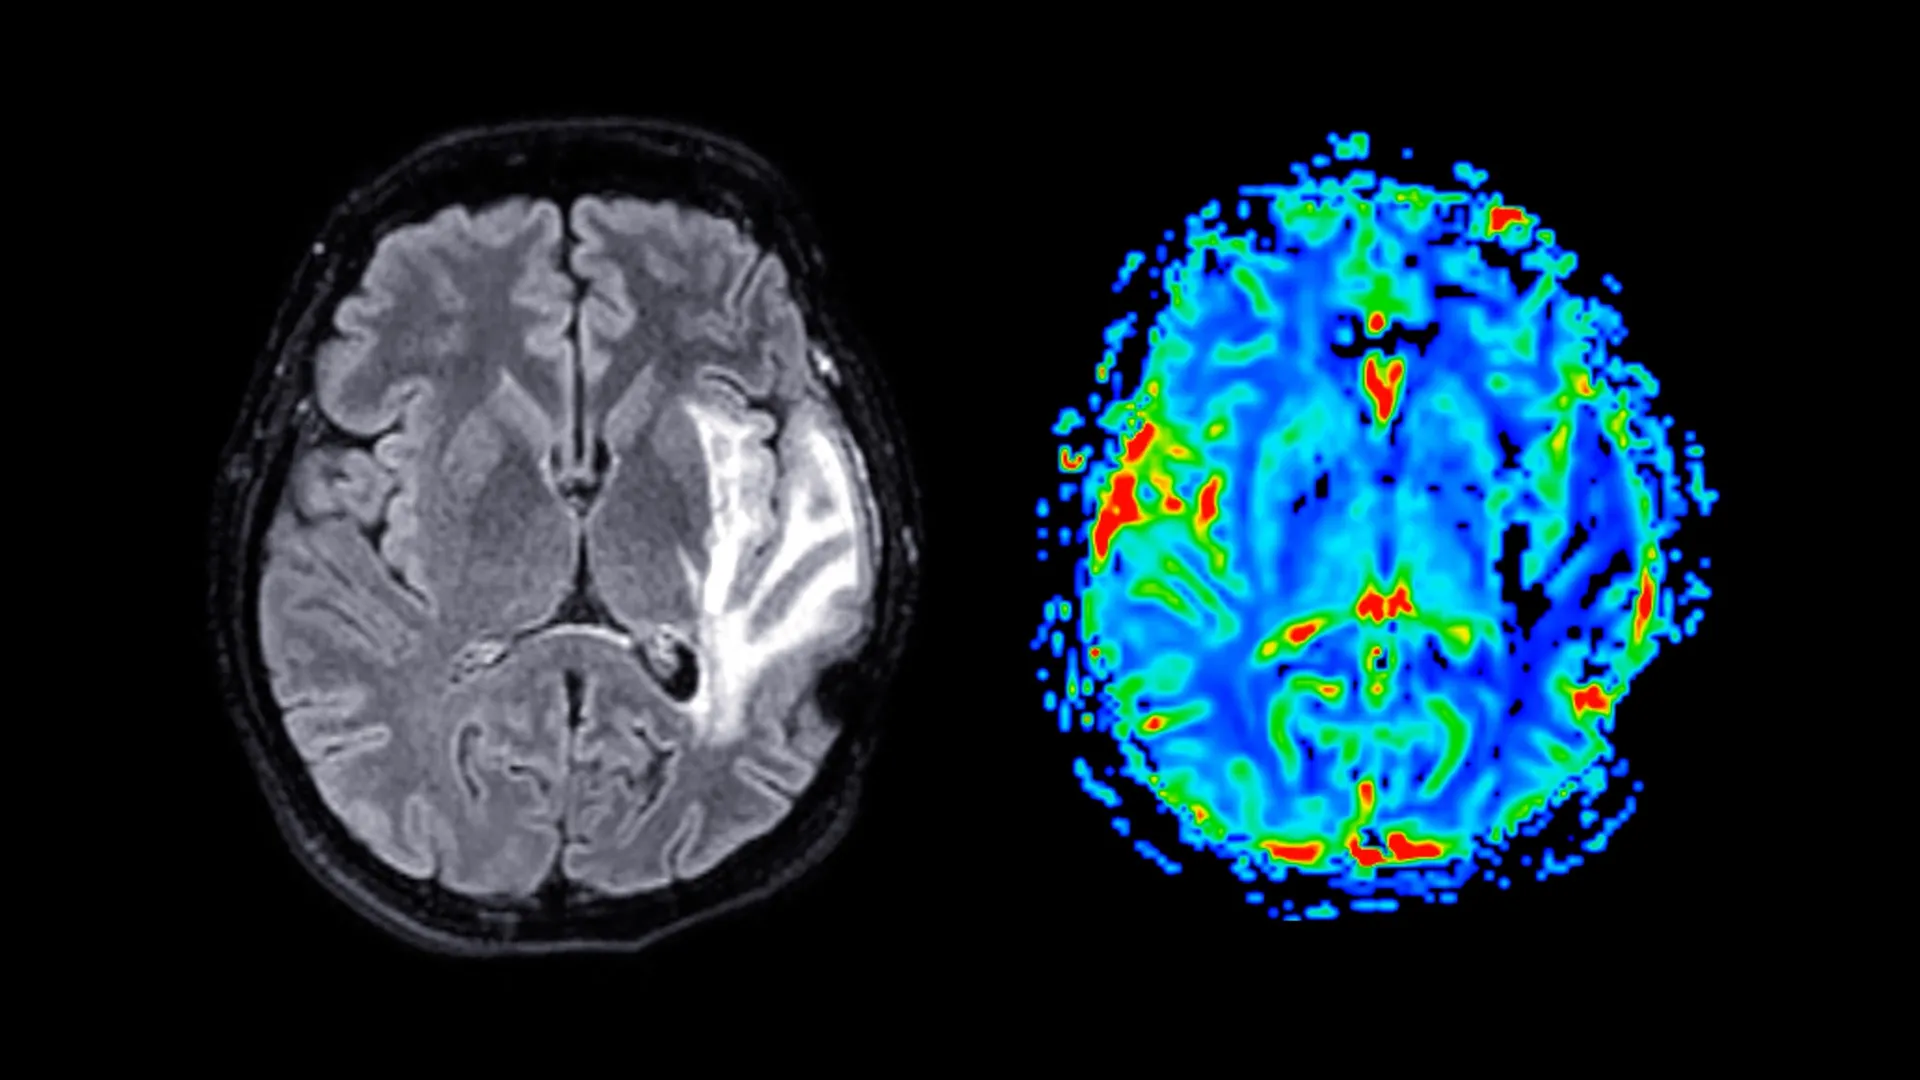

The spectrum of conditions collectively termed "dementia" is multifaceted, with Alzheimer’s disease, vascular dementia, and mixed dementia being the most prevalent forms. These conditions inflict damage upon neural pathways within the brain, leading to a gradual but relentless worsening of symptoms over time. As the neurodegenerative processes advance, individuals may encounter increasing difficulties with communication, orientation, and emotional regulation, presenting a complex and evolving clinical picture.